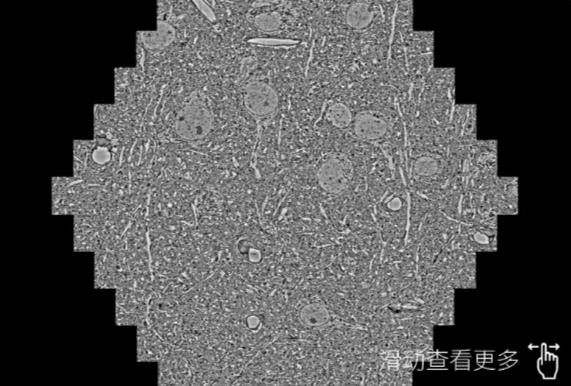

鼠脑切片。左图使用四平蔡司四平扫描电镜MultiSEM706对165μmx143pm面积区域成像,耗时仅需1.5秒。右图为鼠脑切片中30μm区域放大效果。样品由芝加哥大学B.Kasthuri提供。

使用蔡司高速四平扫描电镜MultiSEM对1mm²人脑皮层组织进行高分辨成像,并对其中的各种细胞结构进行三维重构分析。左图展示了2x3mm²组织平面中锥体神经元的三维重构效果。右图显示了局部体积神经元三维重构。图像由哈佛大学chtman实验室提供,渲染图由D. Berger 制作。